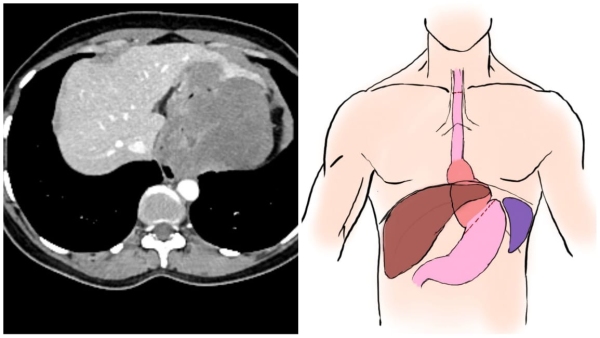

एम्स अस्पताल के कैंसर विभाग में आहार नली और अमाशय की एंडोस्कोपी जांच के बाद, उभार पाए गए ट्यूमर के बारे में पता चला। उस ट्यूमर को लीवर के बाएं हिस्से से चिपका हुआ पाया गया। कैंसर सर्जरी विभाग के सहायक प्रोफेसर, डॉ अंकित जैन ने इसके ऑपरेशन का निर्णय लिया, जो इस प्रकार के ट्यूमर का एकमात्र इलाज था।

ऑपरेशन के दौरान, छाती के दाहिने भाग को खोलकर, आहार नली और ट्यूमर को अलग किया गया। इसके बाद पेट को खोलकर, ट्यूमर को अन्य अंगों से अलग किया गया। ऑपरेशन के दौरान कठिनाइयों का सामना करना पड़ा, जैसे कि ट्यूमर के चारों ओर रक्त वाहिकाओं की उपस्थिति और ऑपरेशन के लिए कम जगह। आहार नली और ट्यूमर को निकालने के बाद, नई आहार नली का निर्माण किया गया और उसे गले में जोड़ा गया।